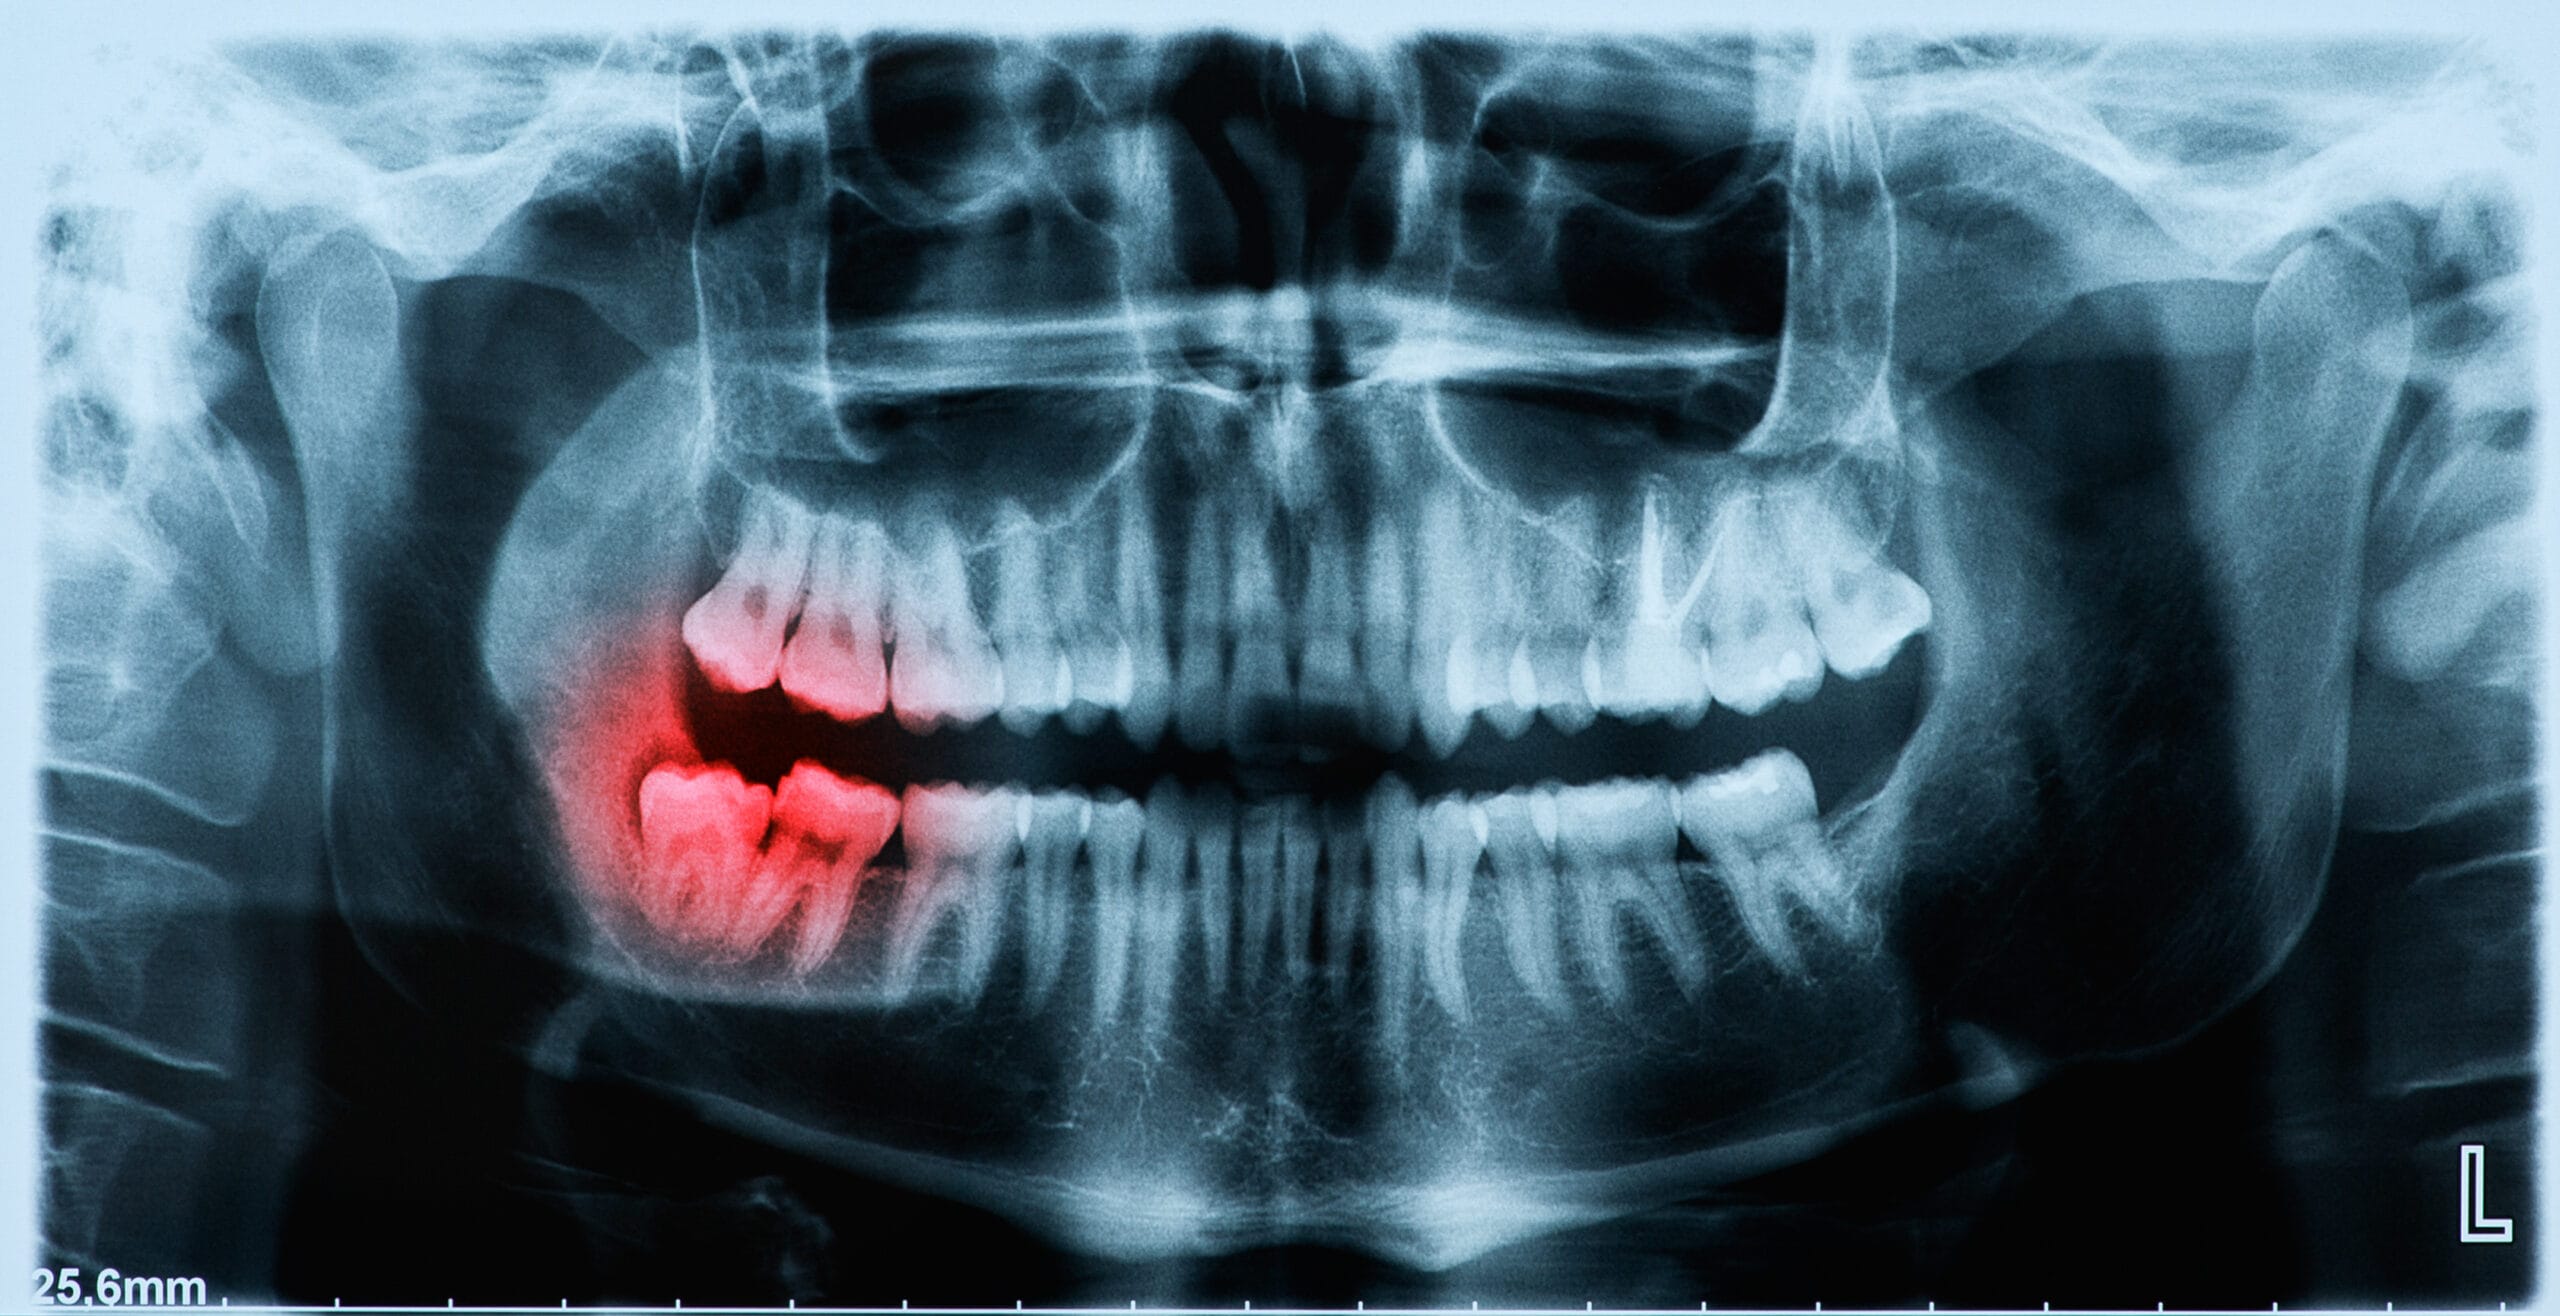

Pericoronitis

An infection that forms around a partially erupted wisdom tooth is known as pericoronitis. The symptoms of pericoronitis can present as inflamed and sore gum tissue, bad breath and an unpleasant taste in the mouth. If left untreated, pericoronitis can lead to the development of a painful abscess, which will require further attention.